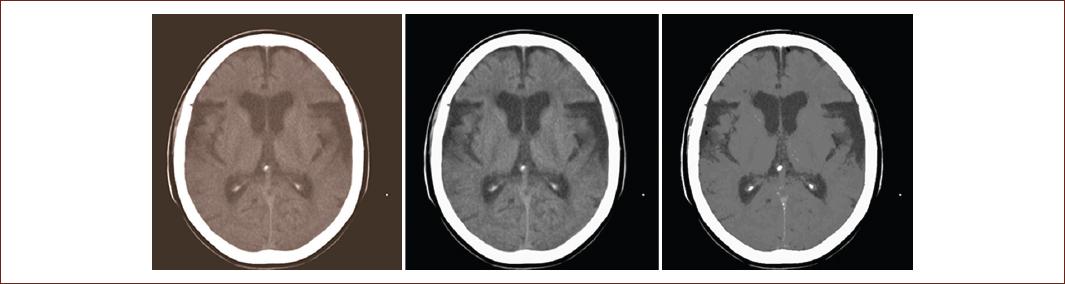

We cannot fail to highlight the importance of the use of computer systems since it allows improving the quality of the visualization of the acquired medical images. Techniques are currently used to reduce the noise produced during image acquisition, enhance specific areas, and segment images into different parts (Fig. 5). Some of these techniques have been developed by academic and commercial organizations, encapsulating them in classroom libraries; an example is the Insight Toolkit open-source library, which specializes in image processing, segmentation, and registration. It is very common nowadays to display the quantitative results made in medical images such as volumetric visualization39.

Figure 5 Left: original Digital Imaging and Communications in Medicine image of a simple raw skull computed tomography. Center: result of applying the curvature flow image filter. Right: result obtained by applying segmentation based on homogeneity indicators during the pre-processing stage (source: taken from the Imaging Department, Juan Bruno Zayas Alfonso Hospital).